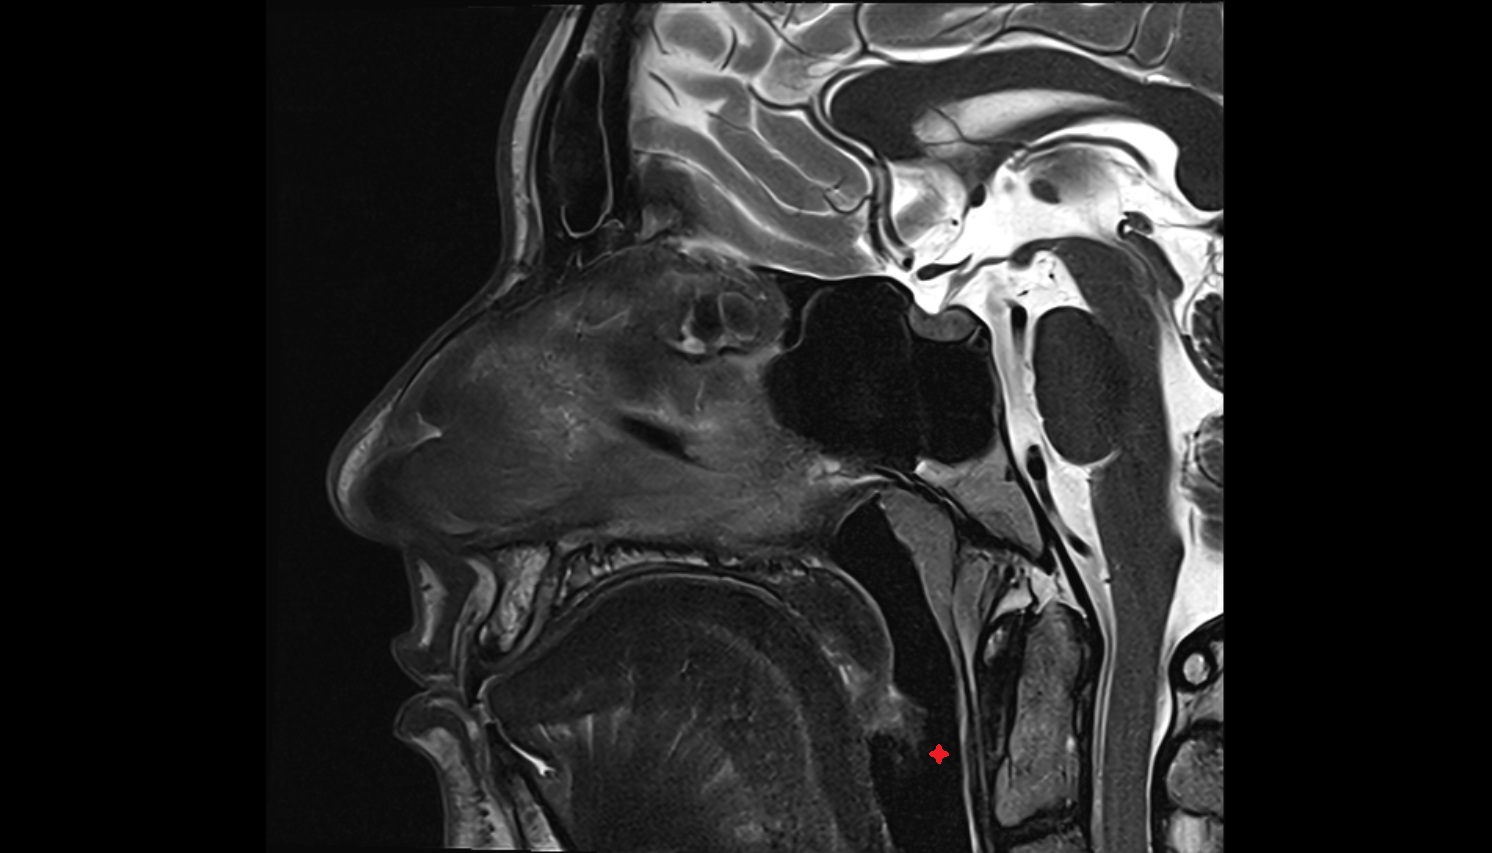

- Epiglottis

- Laryngopharynx

- Nasopharynx

- Oropharynx

- Spinal cord

- Uvula of palate

- Dens of axis

- Hyoid bone

- Thyroid cartilage